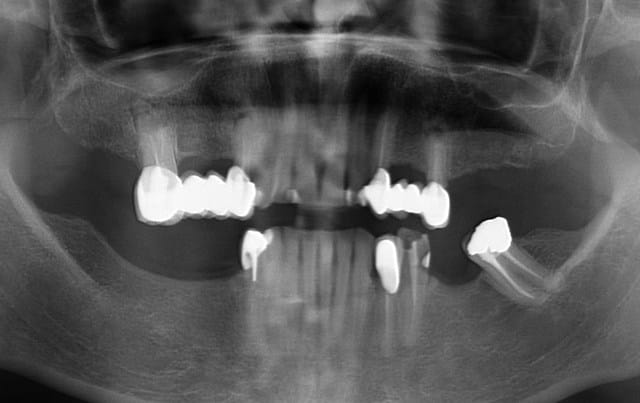

Comme par hasard, ce matin, une patiente (pano jointe) est venue me voir en urgence suite au descellement de sa 34.

(bien sûre les conditions occlusales y sont pour beaucoup : occlusion en bout à bout, édentements postérieurs importants)

> Comme par hasard, ce matin, une patiente (pano jointe) est venue me voir en urgence suite au descellement de sa 34.

> (bien sûre les conditions occlusales y sont pour beaucoup : occlusion en bout à bout, édentements postérieurs importants)